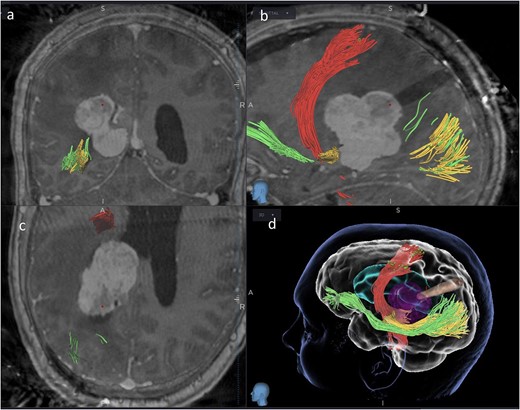

We hereby present the case of a 32-year-old gentleman referred to the neuro-oncology service with an 8-months history of left sided headaches, dizziness, and blurred vision. MRI head demonstrated a 50 × 52 × 51 mm lesion in the posterior horn of the left lateral ventricle, with extension into the periventricular white matter (Fig. 1). Following multi-disciplinary discussion, a plan was made for the patient to undergo a minimally invasive approach for resection of this lesion. Pre-operative cortical and subcortical mapping was performed with navigated transcranial magnetic stimulation (nTMS) and diffusion tensor imaging (DTI). The best trajectory was defined taking into consideration the localization of the cortico-spinal tract (CST, red), the inferior fronto-occipital fasciculus (IFOF, green) and the optic radiations (OR, yellow) (Fig. 2).

Lateral (a), ¾ lateral (b), and posterior (c) views of the pre-operative virtual 3D reconstruction model. The tumour (purple) is reached by the tubular retractor (white) and encircled by the associated white matter tracts: the CST (red) superiorly and anteriorly, and the IFOF (green) and the OR (yellow) that are located inferiorly, laterally, and posteriorly to the lesion.

Coronal (a), sagittal (b) and axial (c) views of the merged images from intra-operative CT scans (O-Arm) with pre-operative MRI tractography. The tubular retractor is in situ. (d) Virtual 3D reconstruction of the tubular retractor (brown) in the merged images and its relationship with the tumour (purple), the CST (red), the IFOF (green), and the OR (yellow).